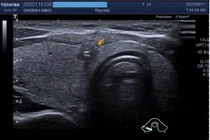

Không có triệu chứng, phát hiện ung thư tuyến giáp 2 bên kèm hạch cổ

Ung thư tuyến giáp tiến triển âm thầm, hầu như không có triệu chứng rõ rệt trong giai đoạn sớm, khiến người bệnh dễ bỏ lỡ “thời điểm vàng” điều trị.

Ung thư tuyến giáp là một trong những loại ung thư nội tiết phổ biến, với tỷ lệ mắc ngày càng gia tăng tại Việt Nam, đặc biệt ở nữ giới. Bệnh thường tiến triển âm thầm, hầu như không có triệu chứng rõ rệt trong giai đoạn sớm, khiến người bệnh dễ dàng chủ quan và bỏ lỡ “thời điểm vàng” để điều trị.

Theo thống kê tại Trung tâm Kiểm tra sức khỏe Chợ Rẫy Việt Nhật (HECI) năm 2023, ung thư tuyến giáp là loại ung thư có tỷ lệ mắc cao nhất ở nữ giới đến khám (hơn 30%), vượt trên các bệnh lý ung thư thường gặp khác như vú, phổi, đại tràng và dạ dày.